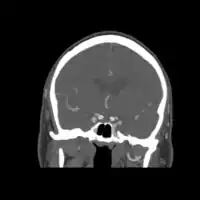

Diagnosis

Diagnosis is by medical imaging, usually a CT scan.[1]